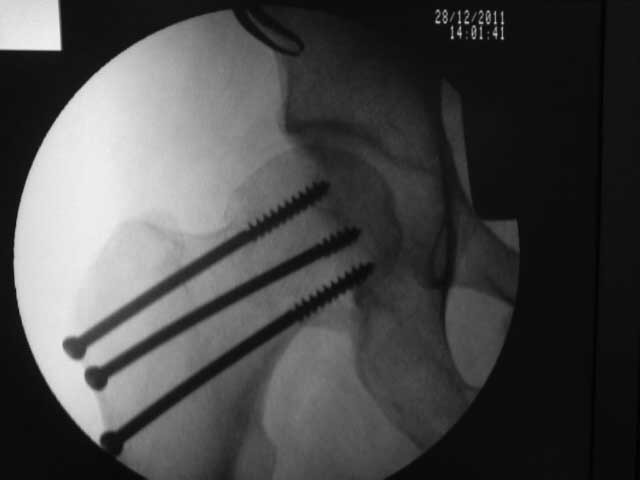

[Ortho] перелом шейки бедра

результат, в конце операции.